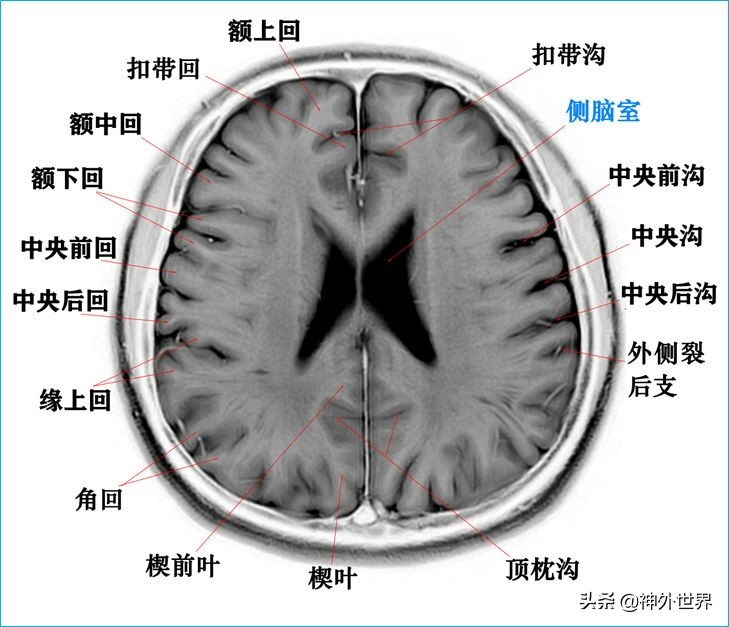

1、水平位连续切片

以下图片均来自我院3.0T核磁共振的T2WI反相图。标注均为我自己完成,水平有限,难免有误,还望各位老师多多指正。谢谢。